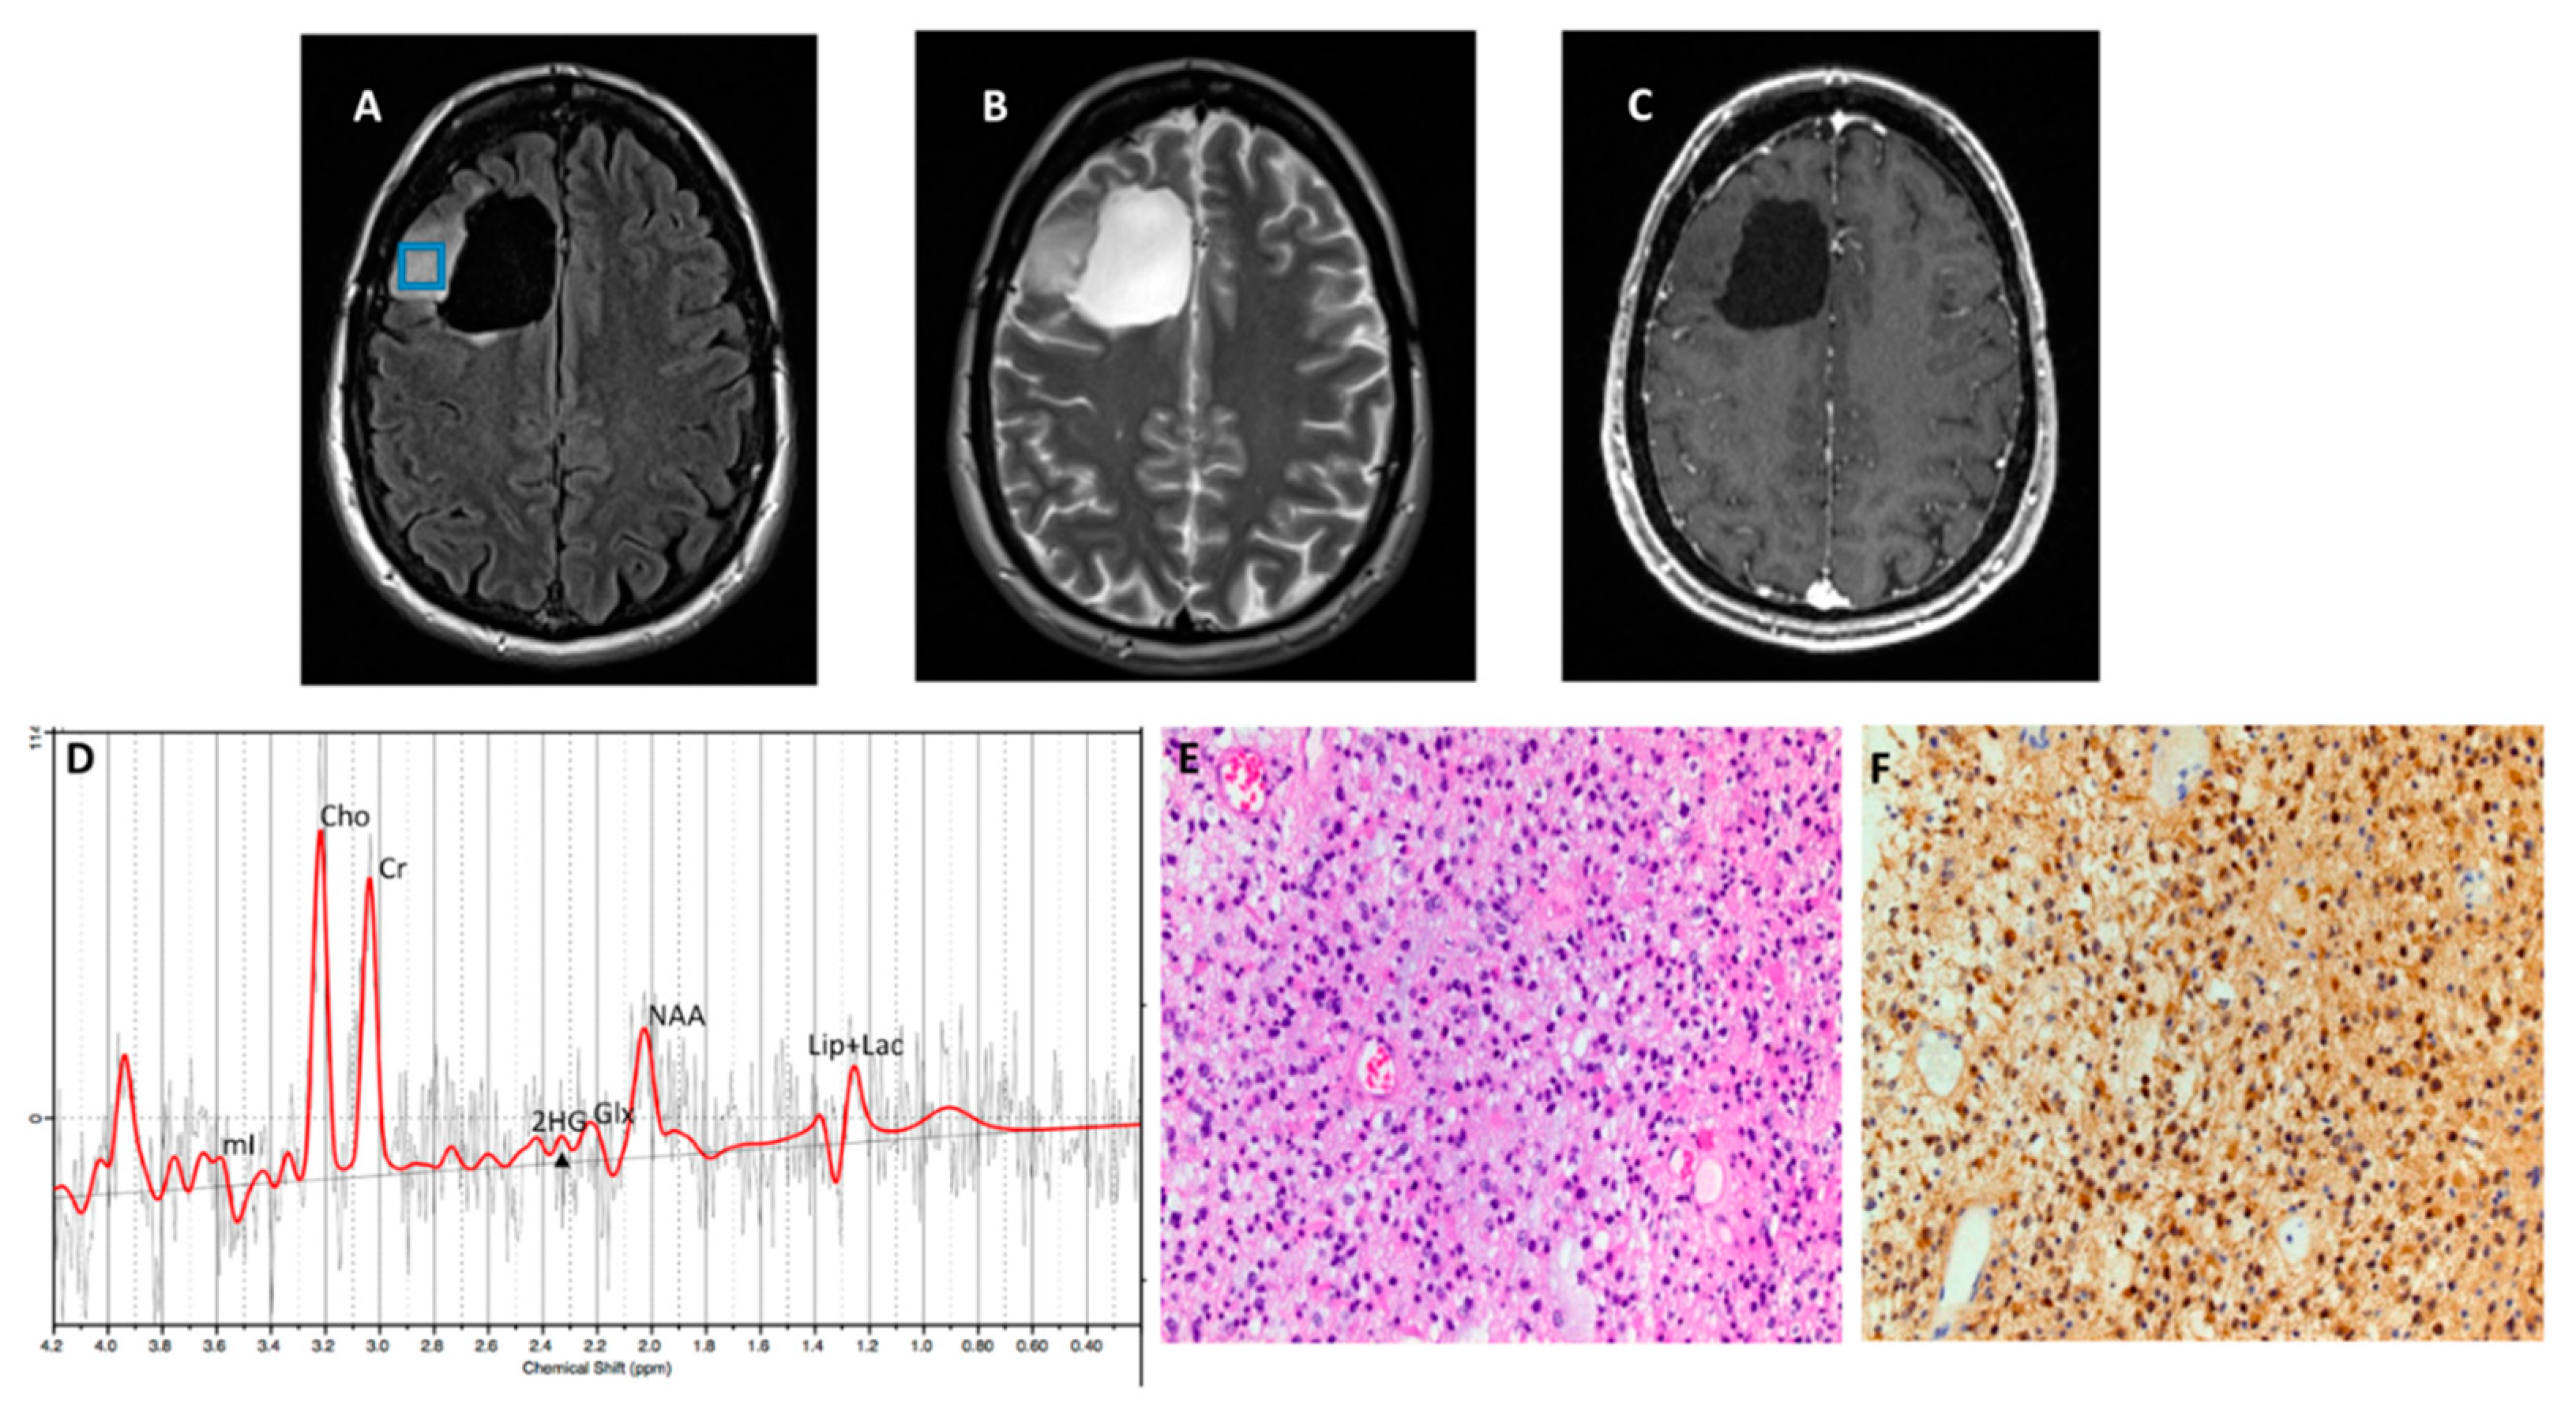

Figure 4. A patient with anaplastic astrocytoma. (A) T2-FLAIR and (B) T2-W show a right temporal lobe mass. (C) Post-contrast T1 shows faint enhancing foci. (D) 1H-MRSI grid overlaid on T2-FLAIR image showing different voxels from tumor (E) Spectra from red voxel (arrow) demonstrates elevated Cho/Cr (0.79; CRLB=3%) and metabolic levels of 2HG (2HG/Cr =1.05; CRLB=16%, black arrow). Histopathological and immunohistochemical analyses were consistent with grade-3 astrocytoma with positive IDH1 mutational status.